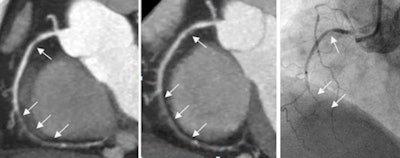

Compared with angiography as the gold standard, CCTA's per-segment sensitivity for diagnosing coronary stenosis of at least 50% was 88.5% at the regular radiation dose with filtered back projection (FBP) and 84.2% using half the dose and iterative reconstruction. Specificity was actually higher at the lower dose, with 92.1% for FBP and 93.4% for iterative reconstruction.

According to the results, the per-segment sensitivity for diagnosing 50% or greater coronary artery stenosis was 88.5% with FBP and 84.2% with iterative reconstruction. Specificity was 92.1% with FBP and 93.4% with iterative reconstruction.

With FBP, the area under the receiver operator characteristics (ROC) curve was 0.903 (95% confidence interval [CI]: 0.881-0.922), compared with 0.888 (95% CI: 0.864-0.909) for iterative reconstruction on a per-segment level.

Compared with FBP, the iterative reconstruction series showed no statistically significant differences (p > 0.05) in subjective image quality analyses, despite a median dose-length product that was 52% lower with the IR protocol than the FBP protocol. Median dose-length product was 109 mGy-cm for the FBP protocol and 52 mGy-cm for iterative reconstruction.